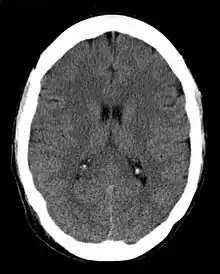

Computed tomography

CT imaging uses X-rays in conjunction with computing algorithms to image the body.[7] In CT, an X-ray tube opposite an X-ray detector (or detectors) in a ring-shaped apparatus rotate around a patient, producing a computer-generated cross-sectional image (tomogram). CT is acquired in the axial plane, with coronal and sagittal images produced by computer reconstruction. Radiocontrast agents are often used with CT for enhanced delineation of anatomy. Although radiographs provide higher spatial resolution, CT can detect more subtle variations in attenuation of X-rays (higher contrast resolution). CT exposes the patient to significantly more ionizing radiation than a radiograph.

Spiral multidetector CT uses 16, 64, 254 or more detectors during continuous motion of the patient through the radiation beam to obtain fine detail images in a short exam time. With rapid administration of intravenous contrast during the CT scan, these fine detail images can be reconstructed into three-dimensional (3D) images of carotid, cerebral, coronary or other arteries.

The introduction of computed tomography in the early 1970s revolutionized diagnostic radiology by providing Clinicians with images of real three-dimensional anatomic structures. CT scanning has become the test of choice in diagnosing some urgent and emergent conditions, such as cerebral hemorrhage, pulmonary embolism (clots in the arteries of the lungs), aortic dissection (tearing of the aortic wall), appendicitis, diverticulitis, and obstructing kidney stones. Continuing improvements in CT technology, including faster scanning times and improved resolution, have dramatically increased the accuracy and usefulness of CT scanning, which may partially account for increased use in medical diagnosis.